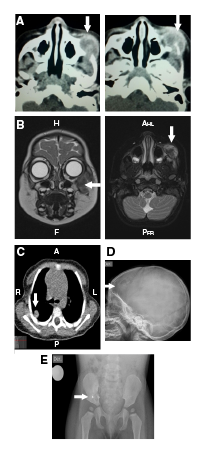

En la tomografía computarizada (TC) de órbita simple y con contraste, se observó una lesión isodensa encapsulada en la región infraorbitaria izquierda (figura 1A). La resonancia magnética (RM) de cráneo, órbita y cuello reveló una lesión tumoral en la región infraorbitaria y la maxilar izquierdas, con compromiso de tejidos blandos e infiltración ósea del maxilar, el arco cigomático y el piso orbitario, con extensión infraorbitaria y extensión al espacio masticatorio, y lesiones nodulares que comprometían la glándula parótida izquierda y la tabla ósea frontal derecha (figura 1B).

Figura 1 A. Tomografia inicial con contraste de órbita simple: se observa una lesión isodensa encapsulada en la región infraorbitaria izquierda que muestra cápsula que capta el medio de contraste. El centro de la lesión es el cuerpo del hueso malar izquierdo que está erosionado y remodelado por la lesión. La lesión erosiona el arco cigomático izquierdo, se extiende a la órbita izquierda y rechaza el globo ocular en sentido central y superior. Sus diámetros son: cefalo-caudal de 2,3 cm, antero-posteriorde 2,2 cm y transverso de 2 cm. B. Resonancia magnética con contraste de cara y cráneo: se aprecia una lesión tumoral en las regiones infraorbitaria y maxilar izquierdas, con compromiso de tejidos blandos e infiltración ósea de maxilar, arco cigomático y piso orbitario, y con extensión infraorbitaria y al espacio masticatorio; se observa una lesión que compromete la tabla ósea frontal derecha. C. Tomografia computarizada simple de tórax: nodulos pulmonares en la periferia del pulmón derecho. D. Radiografía simple de cráneo: lesión lítica de bordes esclerosos y 23 x 15 mm en el hueso frontal derecho. E. Radiografía de pelvis: lesión lítica de bordes esclerosos en de la porción inferior del ilíaco derecho, adyacente a la articulación sacroilíaca, de aproximadamente 25 x 15 mm.

En la TC simple de tórax, se observaron cuatro nódulos pulmonares alojados en la periferia del pulmón derecho y compromiso de la columna vertebral en T4 (figura 1C). La paciente nunca presentó síntomas respiratorios y, dada su edad, no fue posible practicar pruebas de función pulmonar. En la radiografía de serie ósea se encontraron lesiones líticas en cráneo y pelvis, pero no así en los huesos largos (figura 1D).